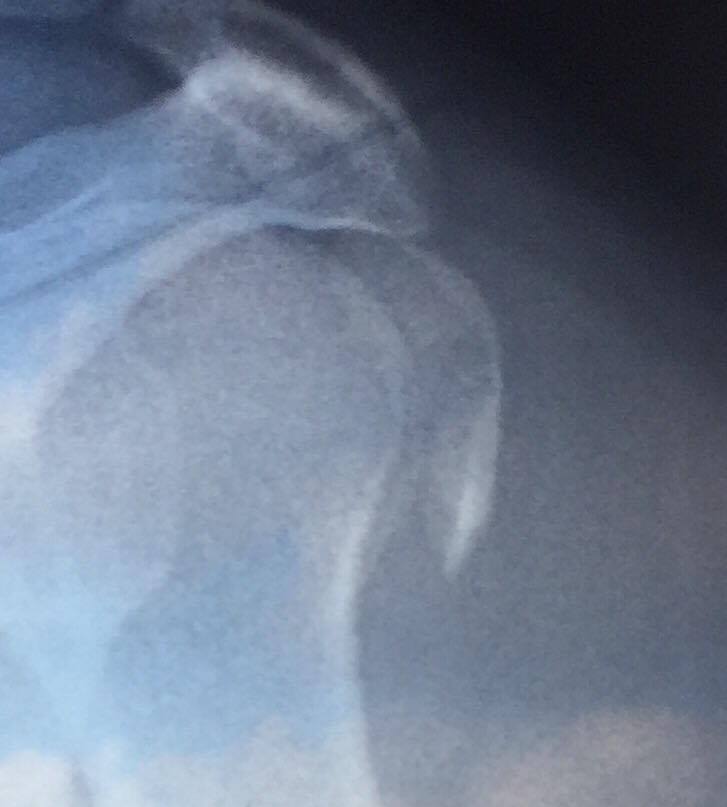

Il 12 settembre scorso è stato portato in ambulanza al Pronto Soccorso di Imperia a seguito di un brutto incidente, e, dopo aver atteso quasi 7 ore, gli è stata diagnosticata una “frattura sottocapitata all’omero sinistro”, non particolarmente preoccupante, per la quale avrebbe dovuto semplicemente portare un tutore per 30 giorni.

Così inizia la storia di Devid Marasco, 28enne di Imperia, che, non convinto del responso dei medici del Pronto Soccorso, dopo pochi giorni ha deciso di andare a farsi controllare in uno studio privato. Dalle lastre di questo secondo controllo, è emerso un quadro molto più grave del previsto, essendo stata diagnosticata sì una frattura del trochite omerale, ma con possibili rischi per i tendini. Di conseguenza, il giovane è stato subito indirizzato verso l‘Ospedale Santa Corona di Pietra Ligure per un’operazione urgente.

Io non mi sono fidato e sono andato a farmi fare le lastre in uno studio privato. Lì mi hanno detto di andare al Santa Corona perché ero da operare urgentemente, visto che un pezzo dell’omero si era spezzato, e, essendo collocato vicino al tendine, rischiavo di non muovere più il braccio.